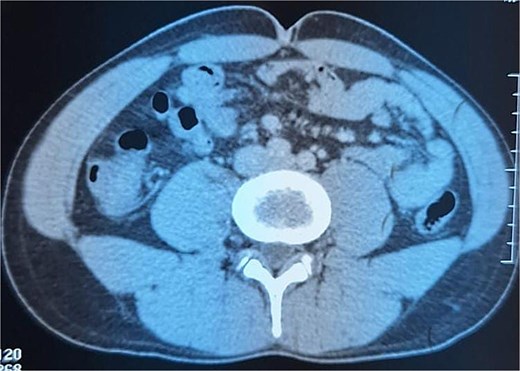

A 29-year-old patient with no significant medical history presented with right iliac fossa pain associated with diarrhea for 4 years, evolving in a context of preserved general condition. Clinical examination revealed tenderness in the right iliac fossa with a good overall state. The biological assessment was normal. The patient underwent a total colonoscopy, which identified non-specific interstitial colitis. An abdominal computed tomography scan was then performed, suggesting an intraperitoneal mass located in the right iliac fossa, containing calcifications and measuring 37 × 49 mm (Fig. 1). The biopsies were non-contributory. The patient was operated on, and surgical exploration revealed the presence of a small intestine tumor invading the base of the cecum. An ileocecal resection was performed (Fig. 2). Histological examination showed a tumor proliferation of fibroblastic nature with variable cellular density, including areas of hypocellular fibrous collagen. There was also an associated lymphocytic inflammatory infiltrate and calcifications. To rule out the diagnosis of gastrointestinal stromal tumors, the main differential diagnosis, immunostaining with anti-CD117 antibody was conducted. The tumor did not express this antigen. The diagnosis of calcifying fibrous tumor was retained.

Intraperitoneal mass located in the right iliac fossa, containing calcifications.